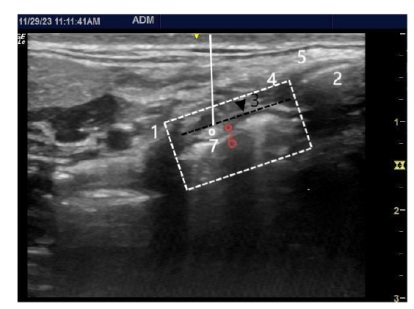

陈哲平, 金延武, 冯昌, 等. 超声引导下喉上神经阻滞研究进展[J]. 临床麻醉学杂志, 2022, 38(6):648-653.

CHEN Z P, JIN Y W, FENG C, et al. Research progress of ultrasound-guided superior laryngeal nerve block[J]. J Clin Anesthesiol, 2022, 38(6):648-653. doi:10.12089/jca.2022.06.017.